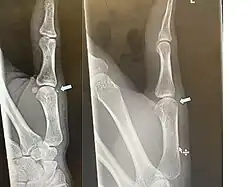

X-ray of an avulsion fracture of the head of the first (thumb) metacarpal on the left hand of a 16-year-old male, images taken one day and seven weeks after the injury, respectively.

If the fracture is small, it is usually sufficient to treat with rest and support bandage, but in more severe cases, surgery may be required. Ice may be used to relieve swelling.[6]

Displaced avulsion fractures are best managed by either open reduction and internal fixation or closed reduction and pinning. Open reduction (using surgical incision) and internal fixation is used when pins, screws, or similar hardware is needed to fix the bone fragment.